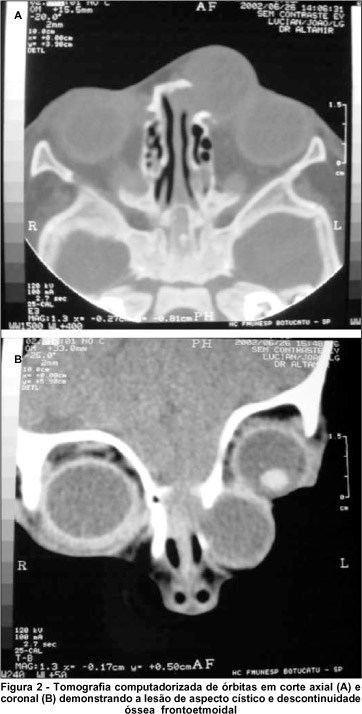

A tomografia computadorizada de crânio e órbitas mostrou uma imagem cística de aproximadamente 2,0 X 2,0 cm, com halo hiperdenso e hipodensidade central. A lesão se apresentava adjacente a uma falha óssea, caracterizada por uma descontinuidade entre o osso frontal e o etmóide esquerdo (Figura 2), confirmando o diagnóstico de uma meningocele fronto-etmoidal. Não se observou córtex cerebral herniado pela falha óssea.

No presente caso, o exame tomográfico foi decisivo para o diagnóstico, mostrando falha óssea que permitia a herniação da meninge para a região orbitária, caracterizando a lesão cística como meningocele. A tomografia computadorizada constata também o defeito ósseo e outras possíveis anomalias, como hidrocefalia, agenesia do corpo caloso, entre outras. A criança em questão apresentava atraso do desenvolvimento neuro-psico-motor, ainda em investigação.